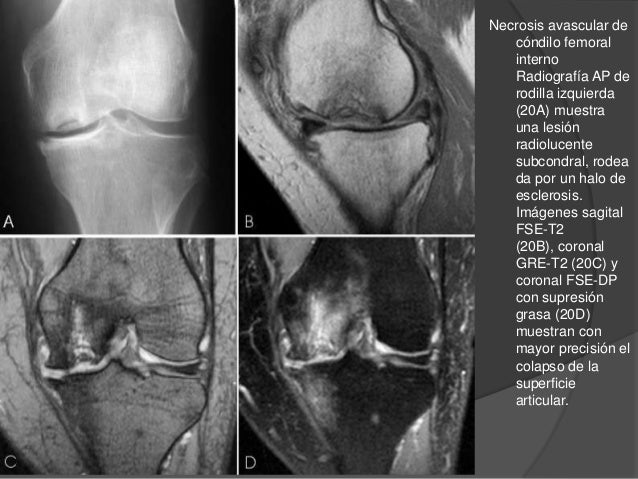

Qu es la osteonecrosis?

Es una entidad patolgica en la cual existe un defecto tanto en el cartlago articular como en el hueso adyacente a l. Espinas tibiales y espacio articular, en comparacin con la radiografa AP sin carga. Excavadoras usadas de segunda mano para su venta - Mascus. Gueyma ha producido este vdeo para sus redes sociales ilustrando la operacin de cambio de la batera de una carretilla elevadora elctrica. Juego de 2 caballetes segunda mano CAT de gran capacidad.

Clnica Traumacor Traumatlogos Corua Lesiones osteocondrales